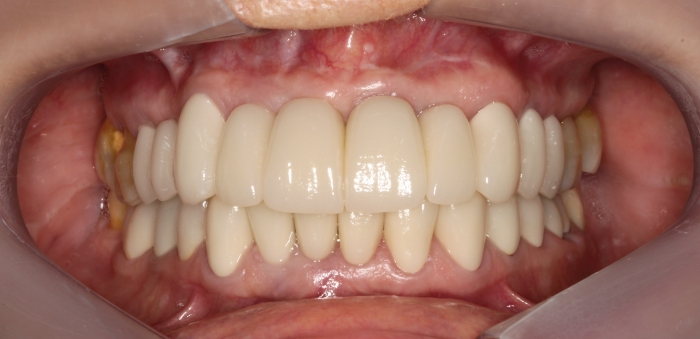

Foto intra oral final 2019

Foto intra oral frontal final 2019